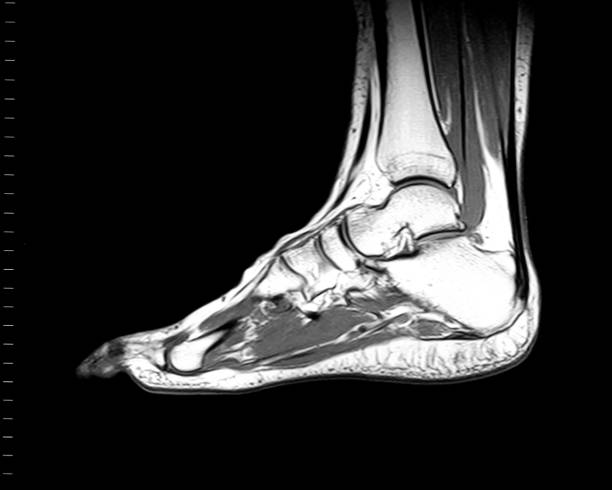

Imaging modalities such as ultrasound or MRI can measure plantar fascia thickness. In healthy individuals this is typically ~2–4 mm (0.2–0.4 cm), while in symptomatic plantar fasciitis it often exceeds 4–5 mm. Thickening combined with changes in echogenicity or signal can suggest degeneration or pathology, though thickness alone cannot reliably distinguish acute from chronic changes.